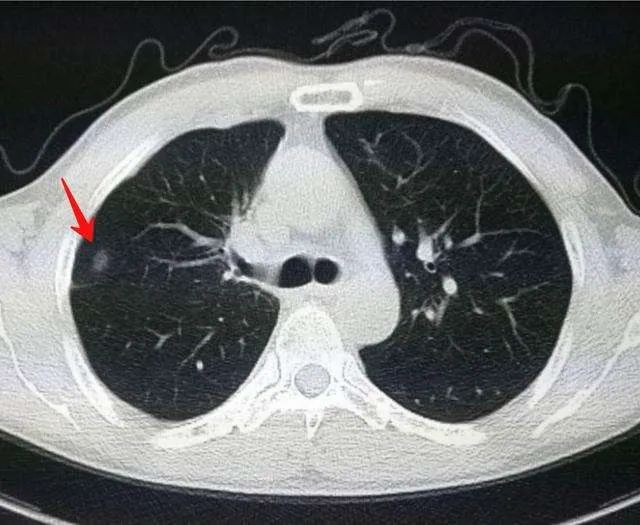

肺結節究竟是什麼玩意呢?所謂的肺結節,就是做胸部CT檢查發現肺臟裏的密度增高的結節(小於3公分)。

胸部CT:紅色箭頭所指為肺結節

(黑的是肺,白的是結節)